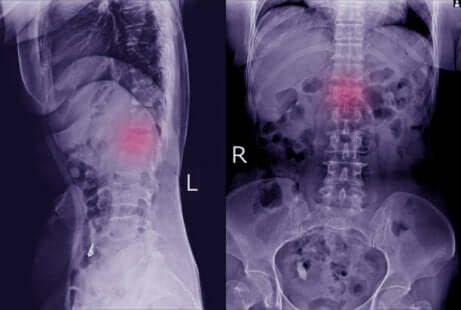

Ces manifestations physiques peuvent passer inaperçues. Toutefois, si nous y sommes attentifs, cela nous permettra d’aller chez le médecin afin qu’il réalise l’un des principaux examens efficace pour son diagnostic : les rayons-x. Il sera donc possible de voir s’il y a un déplacement de vertèbre.

Dans certains cas, le médecin peut exiger des examens plus précis tels qu’une tomographie informatisée ou un scanner à résonance magnétique. Grâce à ces tests, il est possible d’observer plus clairement les cas de spondylolisthésis. Et si elle a également affecté les os et les nerfs.